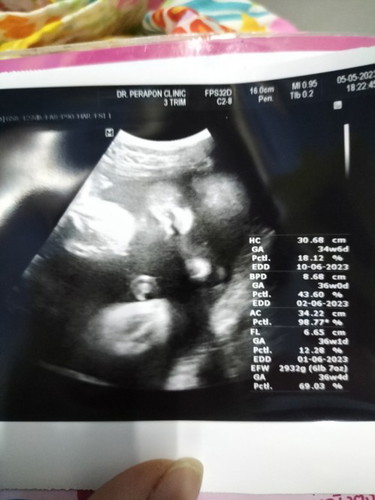

น้ำหนักน้องตามเกณฑ์ไหมคะแม่ๆ

36วีค ไปซาวด์มาหมอบอกน้ำหนัก2932 แล้วค่ะ อยากเจอหน้าแล้ว😊 #ขอบคุณล่วงหน้านะคะ